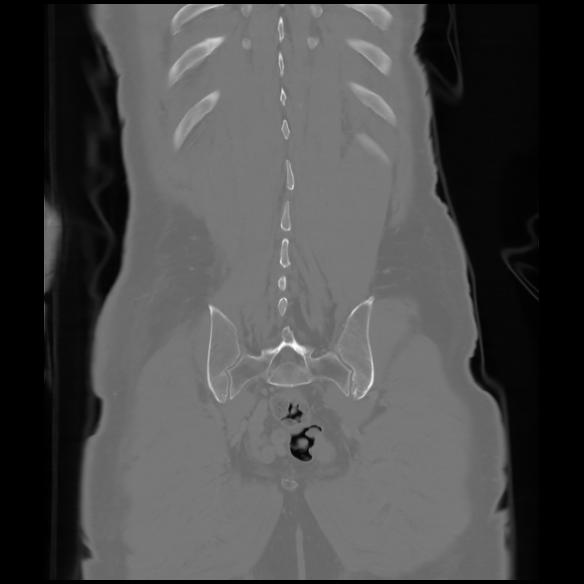

6 CUERPO,CE,Coronal,3.000,CUERPO,Coronal,